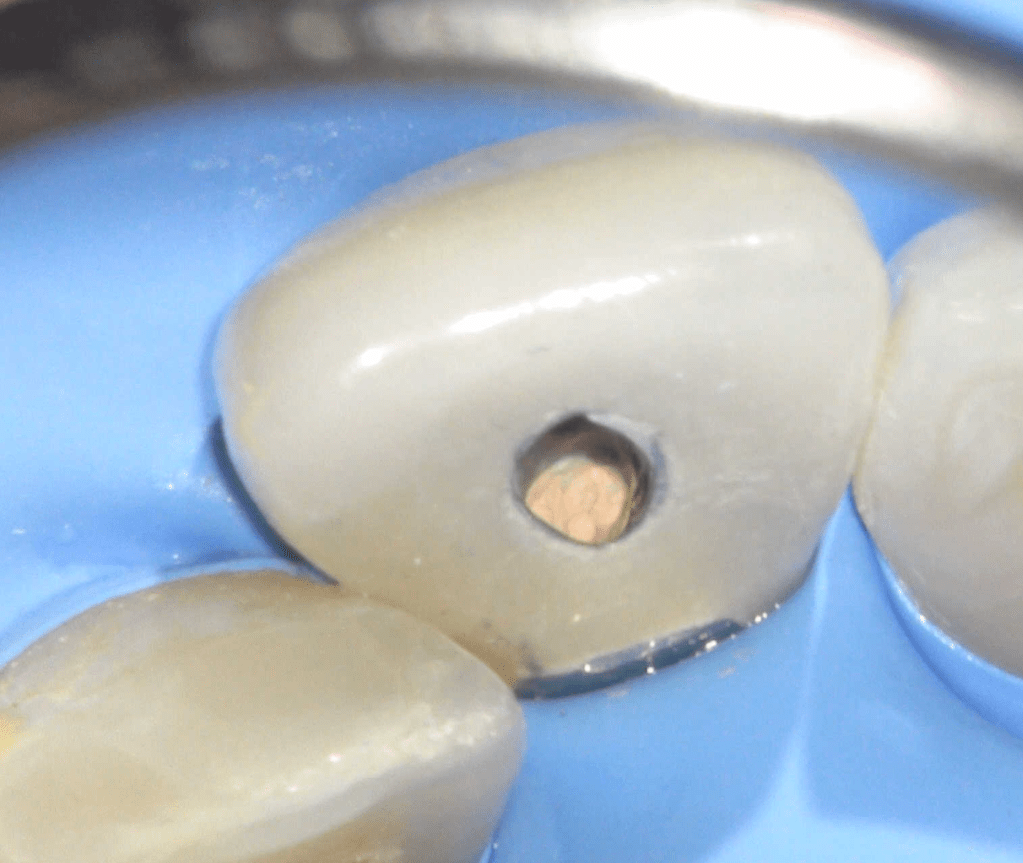

Endodoncias a traves de coronas

Cordal superior pilar de puente